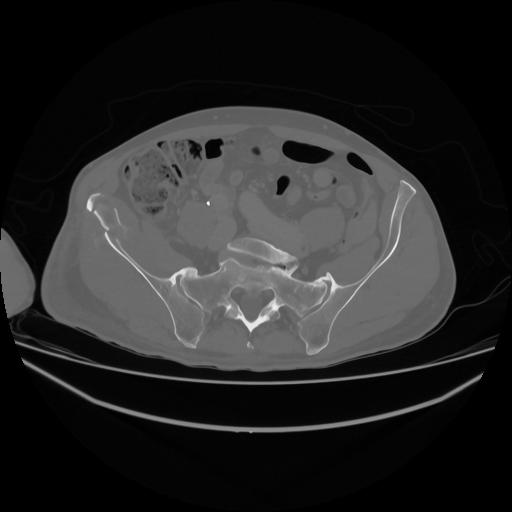

5 CUERPO,CE,Vol,1.0,CUERPO,,